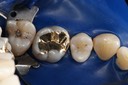

Wayne Chin #14 finish